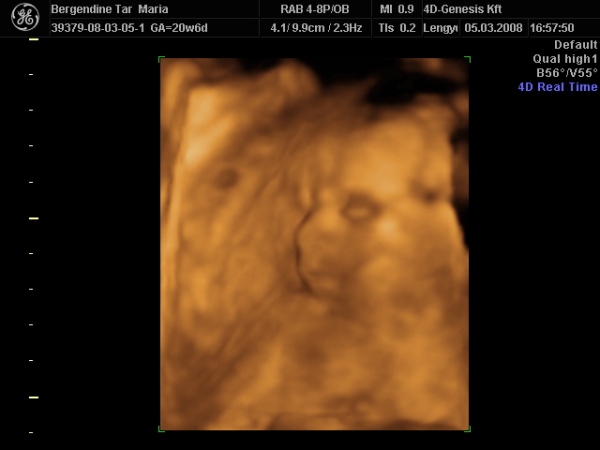

Kis parasztgyerek

Kis parasztgyerek

ez a pólya

ez a pólya